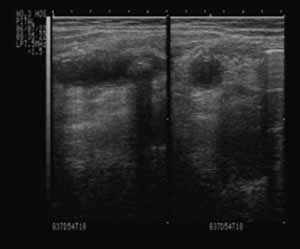

2.2.2 化脓性阑尾炎 阑尾壁仍呈“双边影”,壁厚约0.2~0.6cm,横径>1.0cm,壁明显增厚,黏膜层回声不均匀,体积增大,长约10.0cm左右,腔内可见点状、带状强回声或后有粪石图像(如图2)。

图2